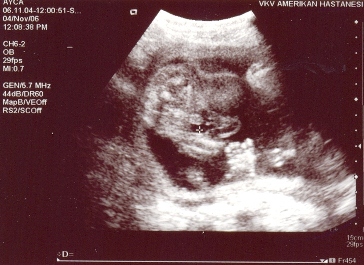

İlk görüntüde ise ayak parmakları,ikinci görüntü önden yüzünün görünüşü.